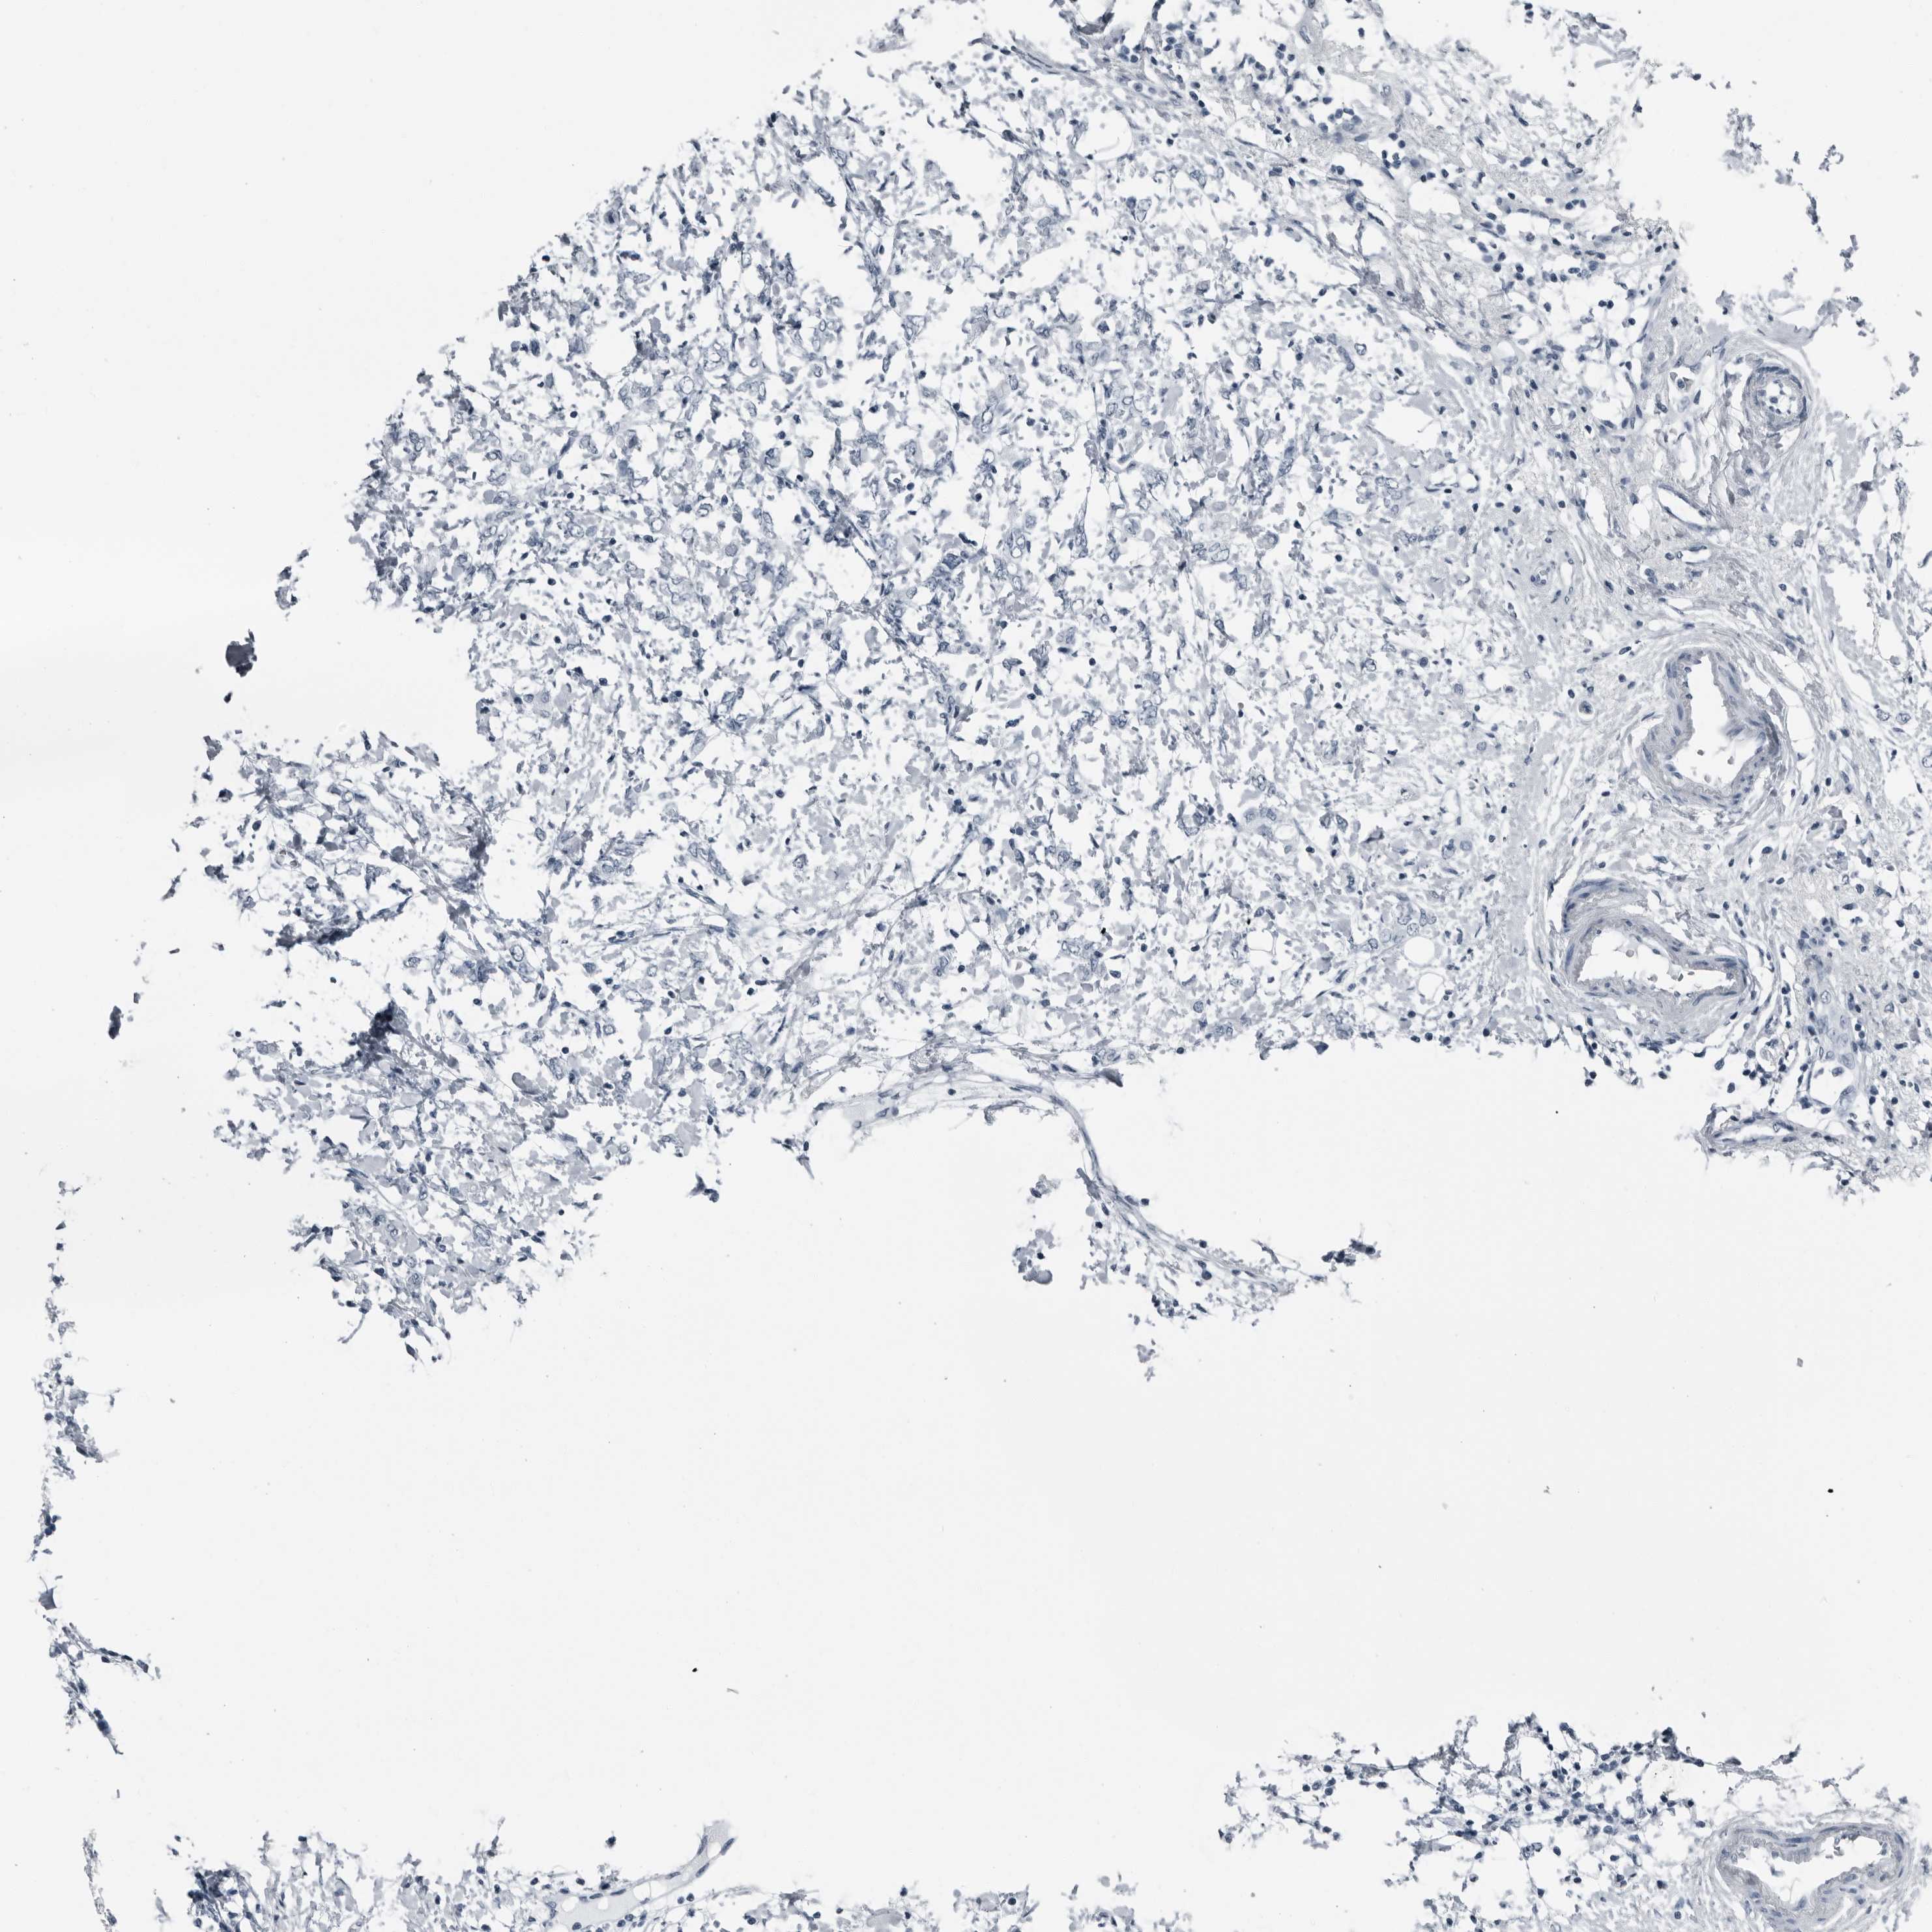

CANCER BREAST CANCER Show tissue menu

BRCA TCGA BRCA VALIDATION PROTEIN EXPRESSION